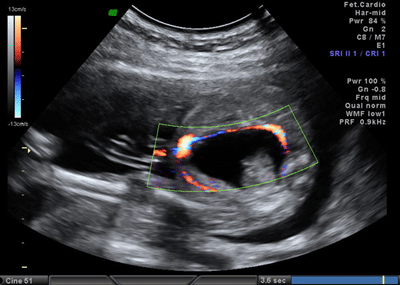

A 26-year-old pregnant women, gravida 1, para 0, was admitted to our prenatal diagnosis centre for detailed ultrasonography examination. Obstetric history was unremarkable. A single fetus was detected at 26 gestational weeks. A presacral located cystic mass measuring 45 × 55 × 40 mm was seen on ultrasound examination (Fig. 1). On doppler ultrasound, the cystic structure with both umbilical arteries around was considered an enlarged distally obstructed fetal bladder initially (Fig. 2). However, the bladder was later identified more superiorly. The amniotic fluid index was 129mm. Diagnosis of the cystic mass was unclear and a fetal MRI was performed, which delineated a large cystic mass with minimal internal echogenicity area, the type IV teratoma (big arrow head). The white arrow demonstrates a cystic mass considered as a hydrometrocolposis (Fig. 3).

Figure 2: The cystic structure with both umbilical arteries around. |